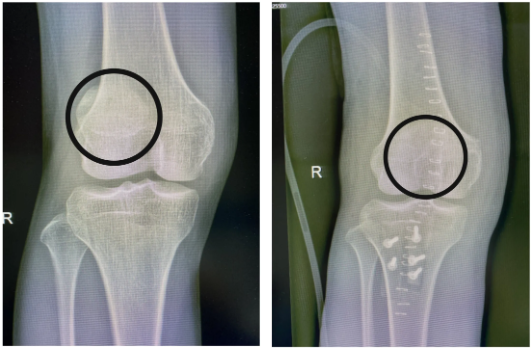

患者术前DR 患者术后DR

经过与患者及其家属的充分沟通后,科室医疗组为其开展“四合一”手术(外侧支持带延长术+Roux-Goldthwait手术+改良Insall近端“Tube”重新排列术+股四头肌滑动/延长术),手术过程顺利,患者“出走的髌骨”成功归位。